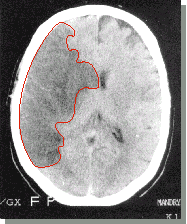

На рисунке рентгенкомпьютерная томограмма головного мозга человека, выполненная через 2 часа после появления клинических признаков острого нарушения мозгового кровообращения.

Выделенный фрагмент - обширный участок пониженной плотности ткани мозга - результат тяжелого повреждения, вызванного тромбозом сонной артерии.